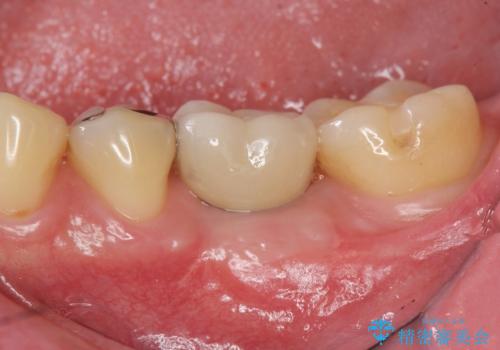

抜歯後、骨の再生を待ったことで、清掃性の高い位置に埋入を行い機能的・審美的なインプラント治療を行うことができました。